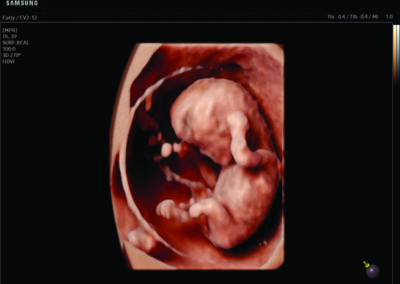

Comprehensive, advanced and expert MFM care for high-risk pregnancies